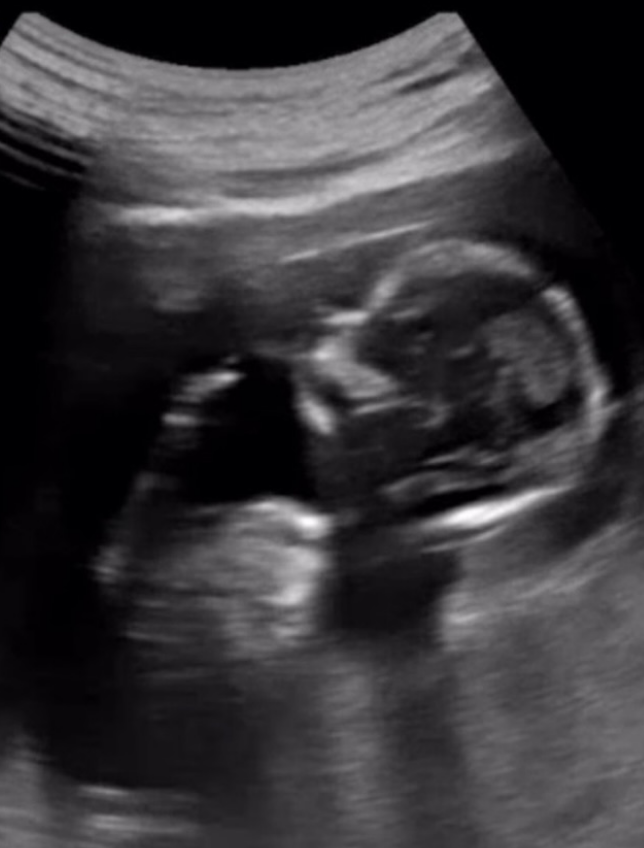

‘수의사♥’ 강아랑, KBS 퇴사 후 깜짝 고백 “엄마 됐다” [IS하이컷]